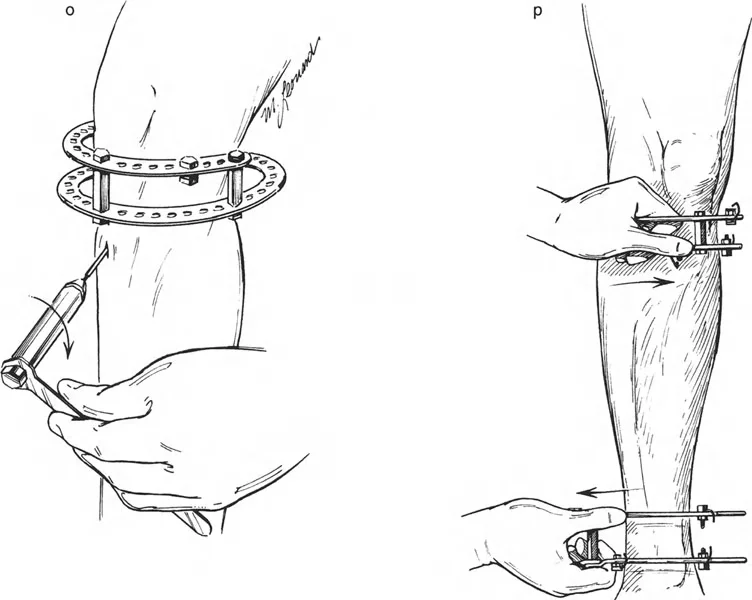

- مثبتات إليزاروف الدائرية الكلاسيكية: تتكون من حلقات معدنية متصلة بالعظم بأسلاك رفيعة، وتسمح بتصحيح متعدد المستويات.

المفصلات القريبة من المفصل وقواعد قطع العظم (Osteotomy Rules)

عند التعامل مع التشوهات الواقعة بالقرب من خط المفصل - مثل التقوس الشديد في الجزء العلوي من الساق (مرض بلونت) أو التشوه الفحجي في الجزء السفلي من عظم الفخذ - يصبح وضع الجهاز مقيدًا هندسيًا. إن المتطلبات البيولوجية للحفاظ على كبسولة المفصل، وتجنب وضع الأسلاك داخل المفصل، ومنع التهاب المفاصل القيحي، غالبًا ما تجبر الجراح على وضع الحلقة المرجعية على مستوى مختلف تمامًا عن مركز دوران الانحراف (CORA) الفعلي.

لمطابقة مفصلة المثبت الخارجي مع المستوى الدقيق لمركز دوران الانحراف (CORA)، يجب غالبًا بناء المفصلة فوق أو تحت مستوى الحلقة الفعلية. يُعرف هذا في مبادئ بالي باسم تجميع المفصلة القريبة من المفصل (juxta-articular hinge assembly).

إذا كان مركز دوران الانحراف (CORA) يقع بالقرب من خط المفصل، فإن وضع حلقة إليزاروف القياسية عند هذا المستوى بالضبط مستحيل دون انتهاك مساحة المفصل أو شد الهياكل الكبسولية الحيوية. لذلك، يتم تثبيت الحلقة المرجعية بالعظم الكثيف أو العظم الطويل المتاح، ويتم بناء آلية المفصلة باستخدام قضبان ملولبة، ولوحات توصيل، ودعامات. ثم يتم "إنزالها" (أو رفعها) لتتطابق تمامًا مع مركز دوران الانحراف (CORA) الهندسي الحقيقي.

إتقان معدلات الشد: قاعدة المثلثات المتشابهة

القاعدة الذهبية البيولوجية لتوليد العظم بالشد، التي وضعها إليزاروف بعد عقود من التجارب على الحيوانات والبشر، هي معدل شد يبلغ 1 ملم يوميًا. يتم تقسيم هذا عادة إلى زيادات قدرها 0.25 ملم كل 6 ساعات لمحاكاة النمو المستمر للوحة النمو.

ومع ذلك، فإن الخطأ الشائع، الذي قد يكون كارثيًا أحيانًا للجراحين المبتدئين، هو سوء فهم أين يجب أن يحدث هذا الـ 1 ملم يوميًا.

معدل 1 ملم/يوم ينطبق بشكل صارم على القشرة المقعرة للعظم في موقع قطع العظم (الحافة الأمامية للإسفين المفتوح). نظرًا لأن الجهاز (قضيب الشد أو دعامة TSF) يقع على مسافة من العظم، خارج غلاف الأنسجة الرخوة، فإنه يتحرك على طول قوس أكبر بكثير. إذا وجهت المريض لشد القضيب بمعدل 1 ملم يوميًا، فإن العظم الفعلي سيُشد بجزء ضئيل من هذا المعدل، مما يؤدي إلى التصلب المبكر لموقع قطع العظم.

حساب معدل الشد الحقيقي

لحساب المعدل الصحيح للشد عند المفصلة، نستخدم قاعدة المثلثات المتشابهة، والتي تعتمد أساسًا على القاعدة الهندسية للدوائر متحدة